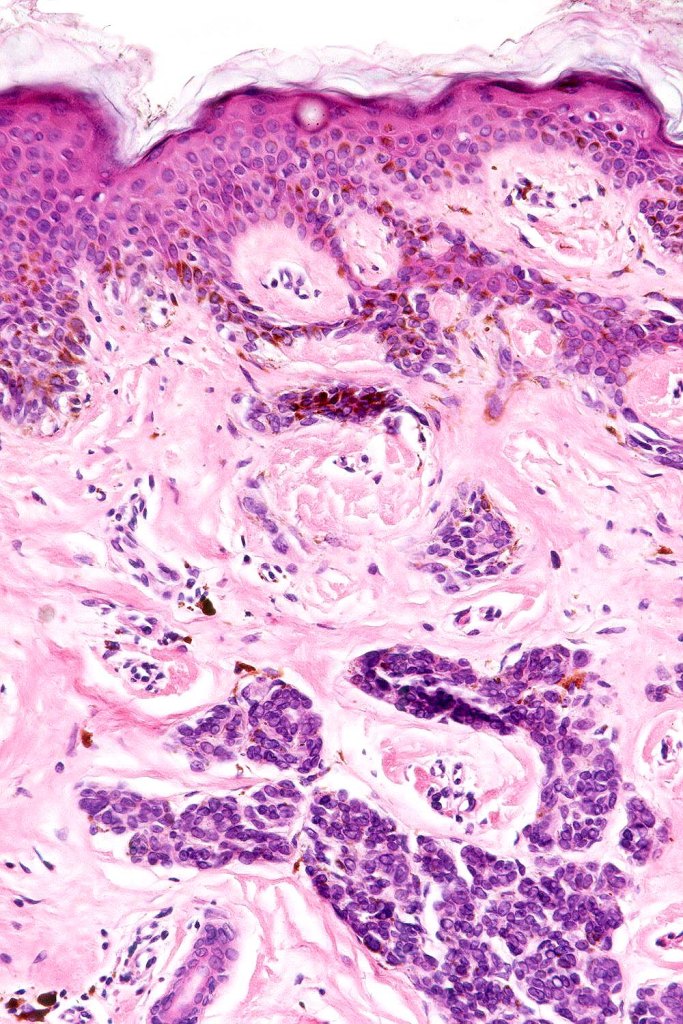

•Large dyscohesive nests with retraction artifact, not restricted to the tips of the epidermal ridges

•Heavy pigmentation (sometimes gray/green)

•Bridging common, often over multiple rete ridges

•Central pagetoid spread

•Superficial dermal atypia

•Junctional mitoses sometimes present, dermal mitoses+/-, can be multiple but never atypical